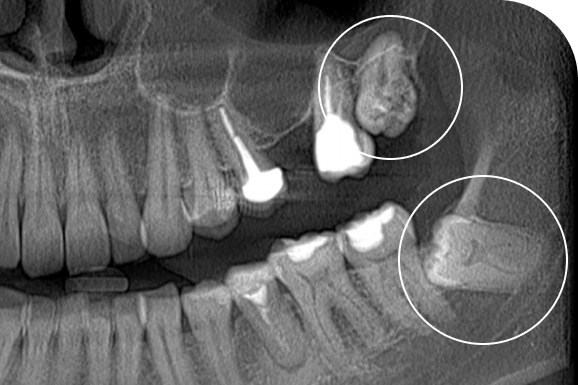

Чаще всего проводится удаление ретенированных и дистопированных зубов — обычно это зубы мудрости, которые не прорезались полностью или растут неправильно. В зависимости от ситуации удаление может быть разной степени сложности. Перед процедурой врач обязательно делает снимок и выбирает оптимальный способ лечения.